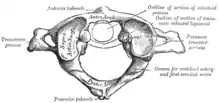

| Image of the first cervical vertebra, which is broken during a Jefferson fracture | |